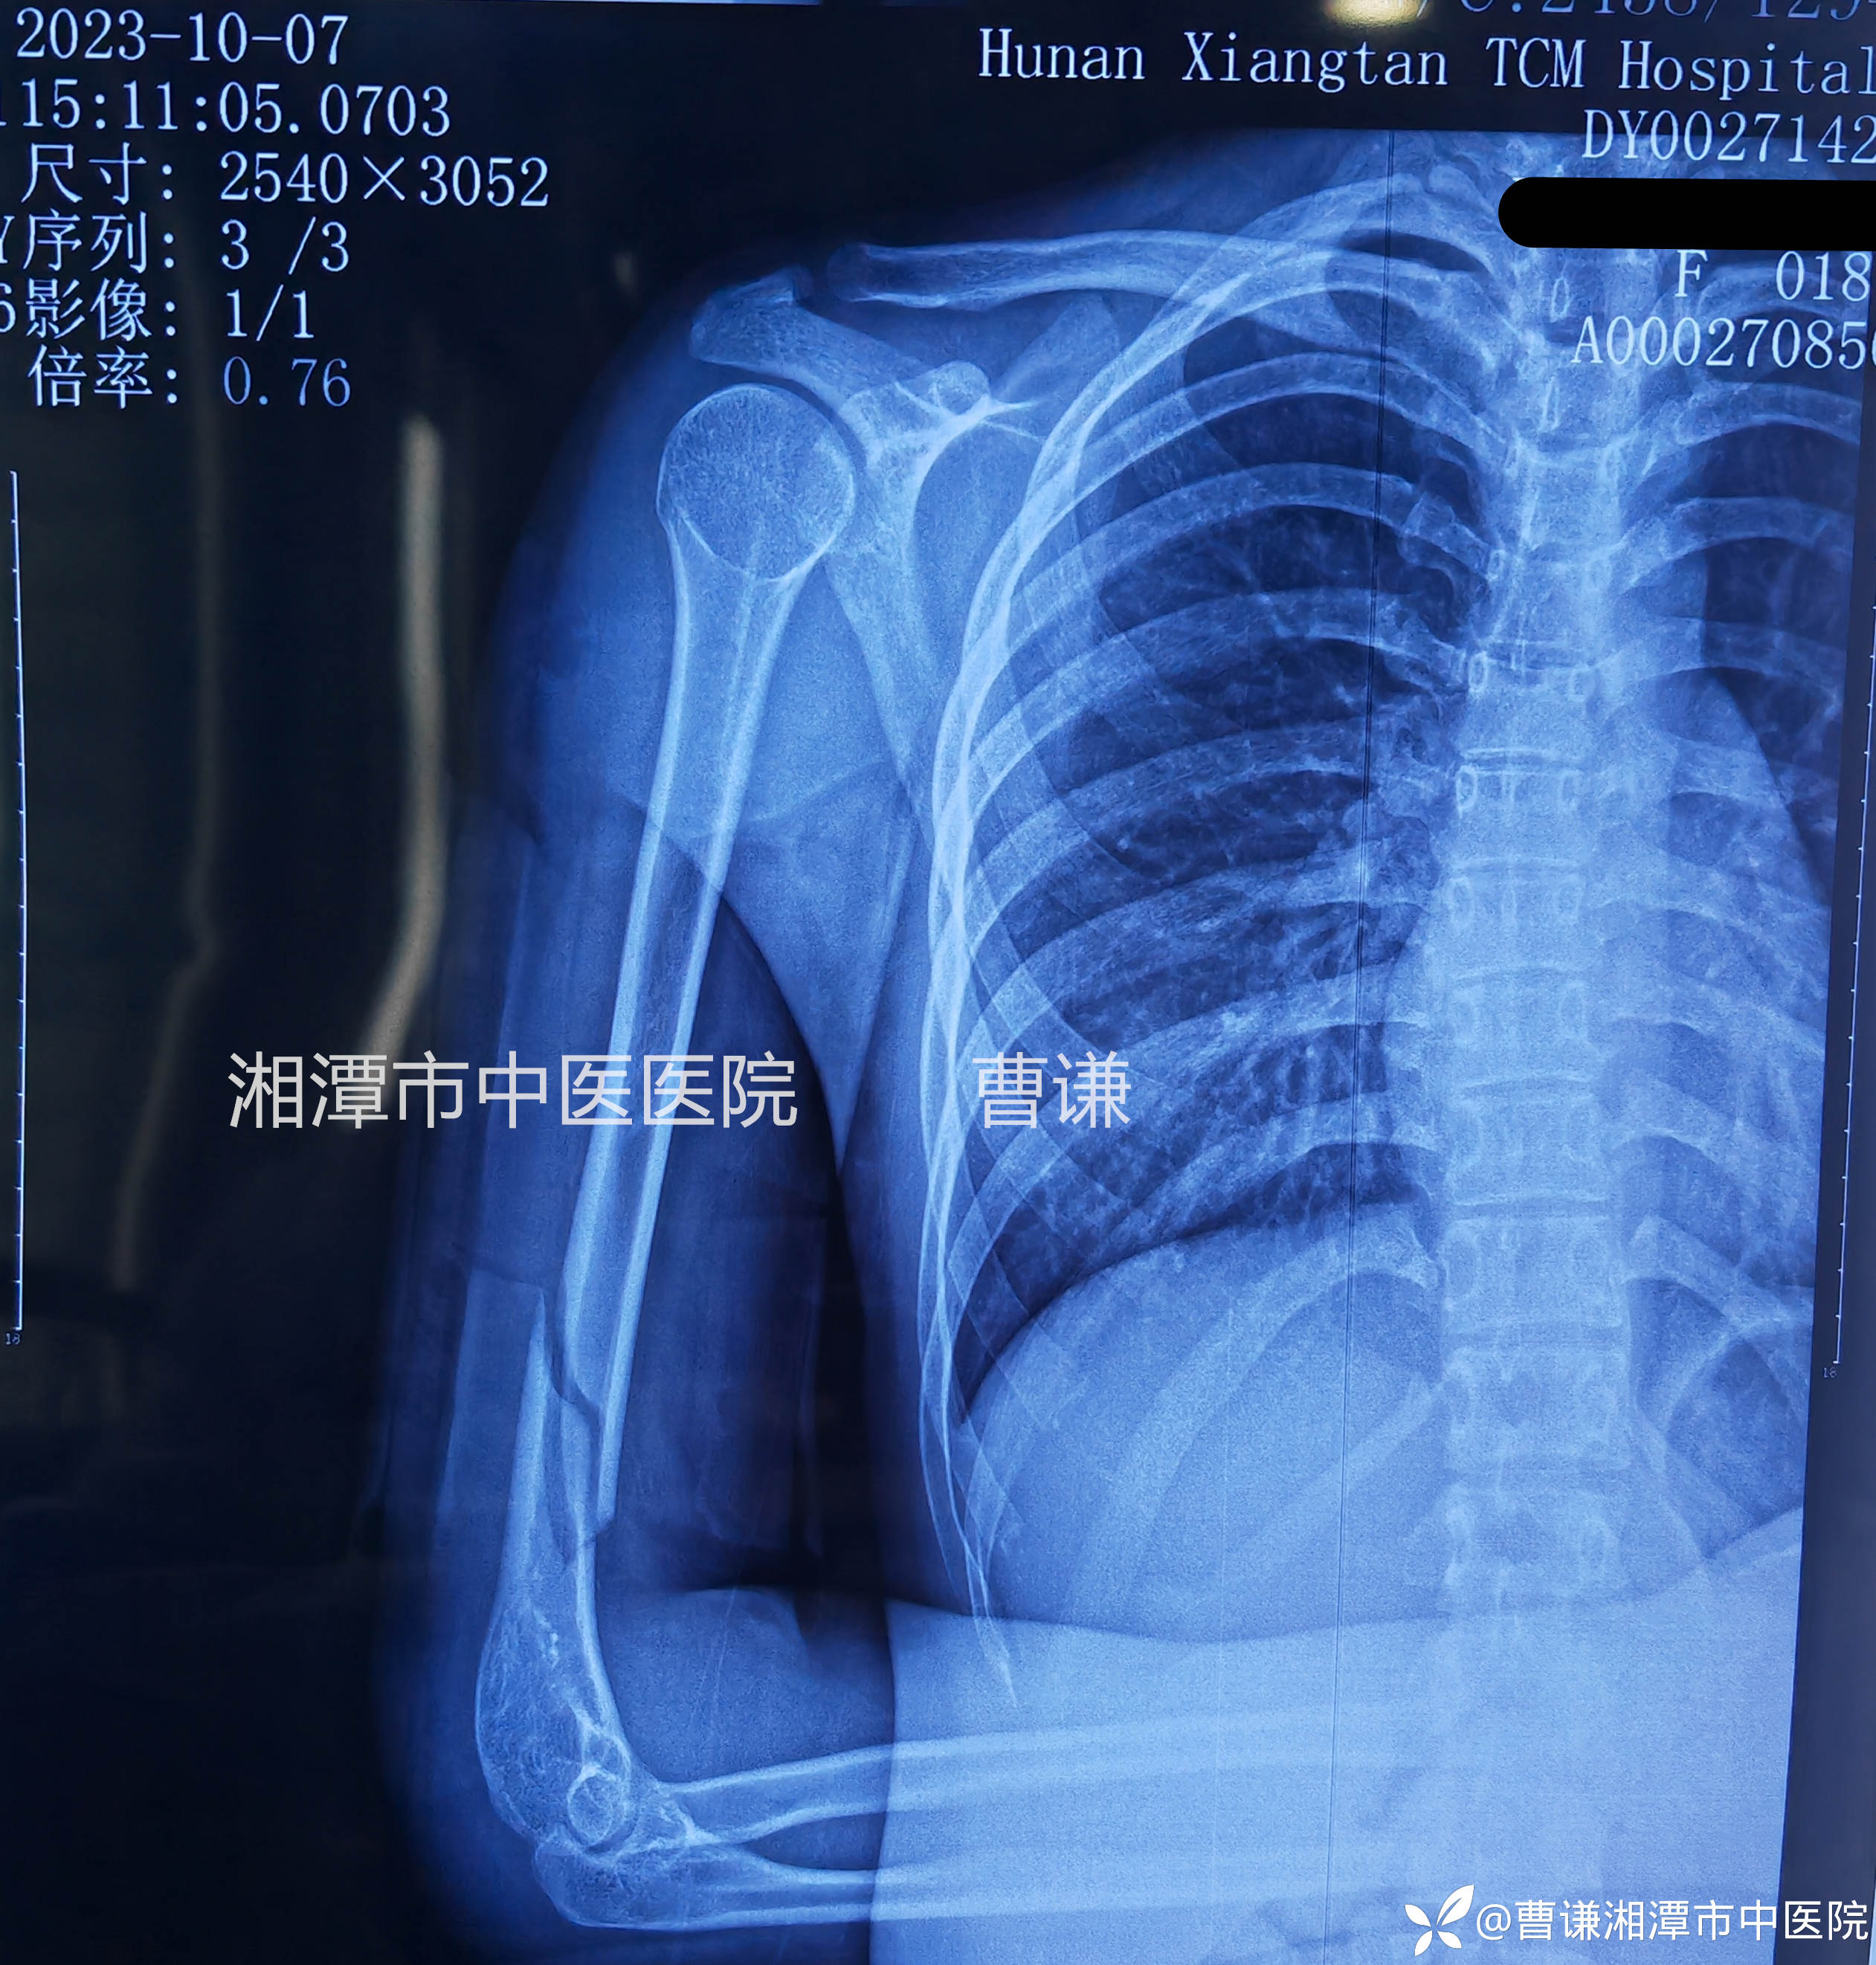

外伤后当地医院拍片情况显示右肱骨中下段骨折

入院后值班医生予以杨氏三步复位法手法复位(具体手法参看——肱骨中上段粉碎骨折的保守治疗)小夹板外固定,拍片复查示骨折对线良好,断端稍有分离,请我阅片后,我认为目前对位对线情况不影响预后,可以继续维持,指导患者积极进行握拳伸掌功能锻炼。